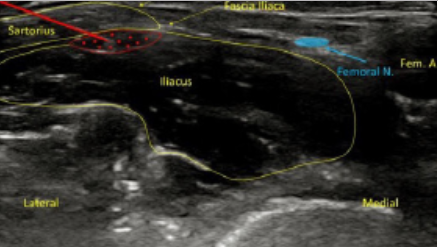

The Suprainguinal View: Sartorius overlies the iliacus muscle on its lateral border, with the fascia iliaca separating the two muscles. The femoral nerve and vascular bundle lie medial to the iliacus muscle, and the lateral femoral cutaneous nerve lies between the muscle bodies.

Note: Approach of needle injection site using the suprainguinal approach is from lateral to medial, parallel to the inguinal ligament. Note the needle track ultimately ends between the fascia iliaca and the iliacus muscle, like in the infrainguinal approach.